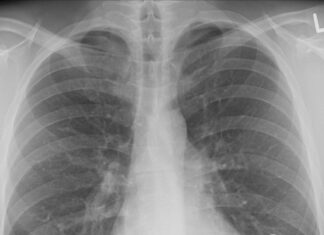

Lungenkrebs: Häufig, tödlich – und noch immer unterschätzt

Zum Weltlungenkrebstag am 1. August lenkt das KLI für Lungenforschung an der Wiener Klinik Floridsdorf den Blick auf die Bedeutung von Aufklärung, Forschung und...